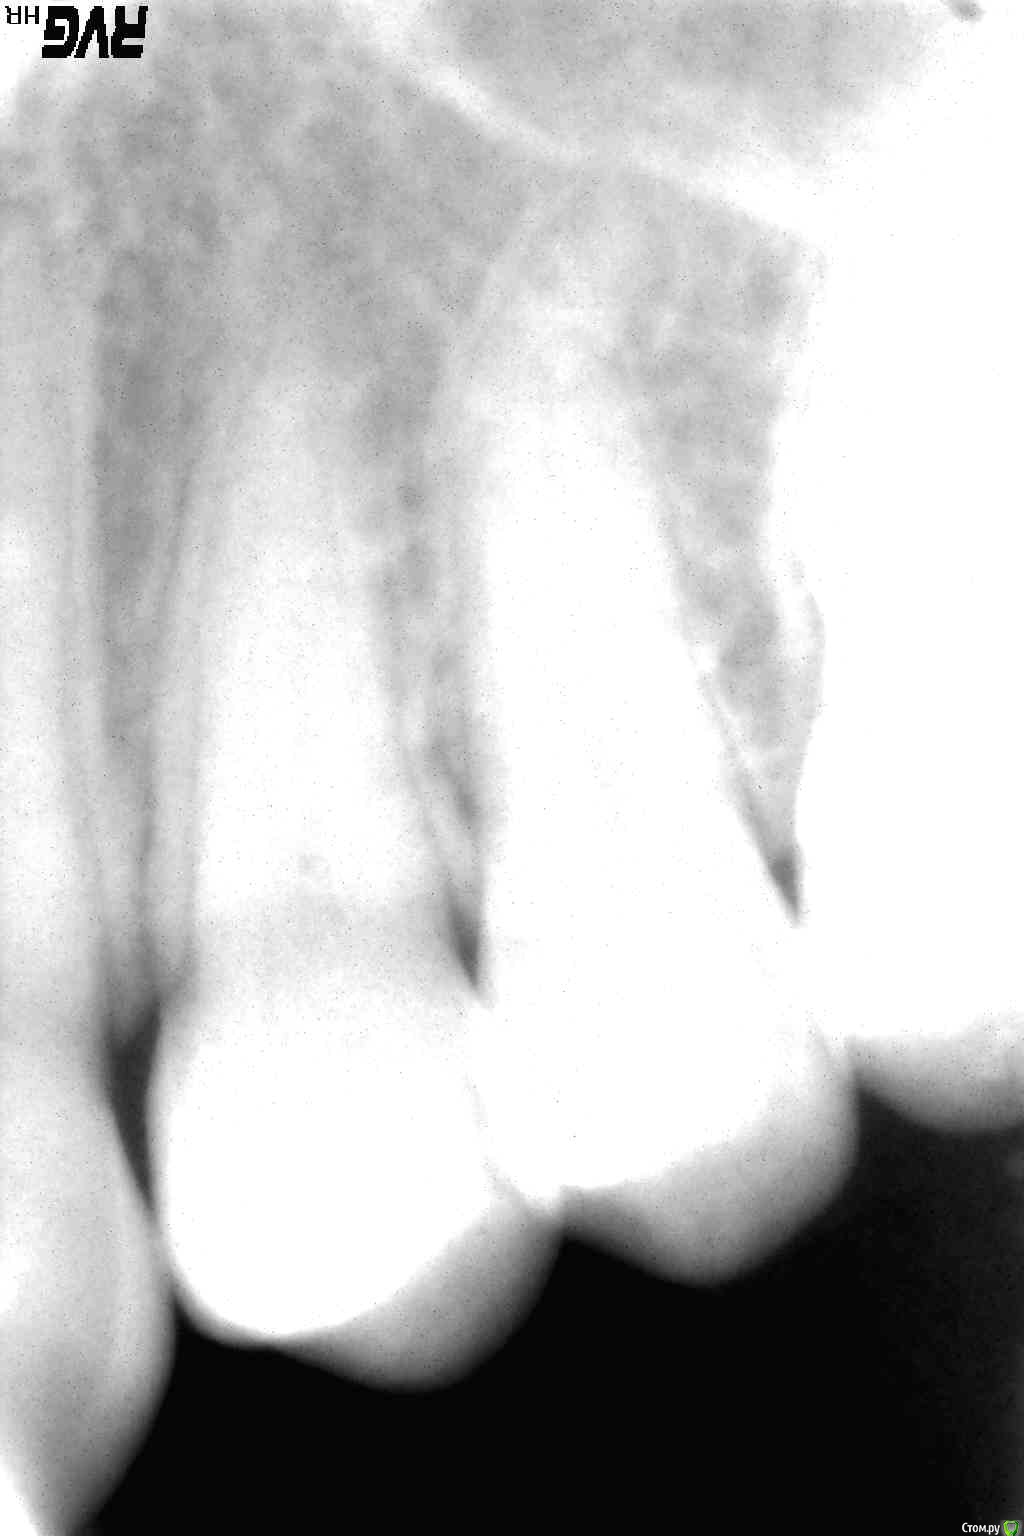

Витторио Орлионе Опубликовано 21 февраля, 2016 Поделиться Опубликовано 21 февраля, 2016 Господа, помогите пожалуйста мудрым советом.Зуб 4.7 был пломбирован 2 года назад и на сегодняшний день не беспокоил, а обратились потому, что скололась пломба на нём и прошло уже 2 дня с момента открытия зуба. В результате осмотра была обнаружена ВАТА. Убрал все поражённые ткани и в итоге зуб было рекомендовано восстановить вкладкой и коронкой. Вопросы:Нужно ли перелечивать каналы?Удалять ли 4.8 зуб? Зуб 2.5 ранее лечен резорцом, сейчас в цвете здорово изменён, да и пломба на нём весьма большая. Рекомендованы вкв и коронка.И тут снова вопрос о перепломбировке, нужно ли это? Вообще весьма непонятны такие случаи, когда надо перелечивать, а когда не надо? Ссылка на комментарий

Ker Опубликовано 21 февраля, 2016 Поделиться Опубликовано 21 февраля, 2016 Господа, помогите пожалуйста мудрым советом.Зуб 4.7 был пломбирован 2 года назад и на сегодняшний день не беспокоил, а обратились потому, что скололась пломба на нём и прошло уже 2 дня с момента открытия зуба. В результате осмотра была обнаружена ВАТА. Убрал все поражённые ткани и в итоге зуб было рекомендовано восстановить вкладкой и коронкой. Вопросы:Нужно ли перелечивать каналы?Удалять ли 4.8 зуб? Зуб 2.5 ранее лечен резорцом, сейчас в цвете здорово изменён, да и пломба на нём весьма большая. Рекомендованы вкв и коронка.И тут снова вопрос о перепломбировке, нужно ли это? Вообще весьма непонятны такие случаи, когда надо перелечивать, а когда не надо?На цемерке похоже на периодонтит качественный. Стоит попробовать, имхо. Пятерку тоже стоит, тем более если вкладка нужна. Снимок так себе кстати. Ссылка на комментарий